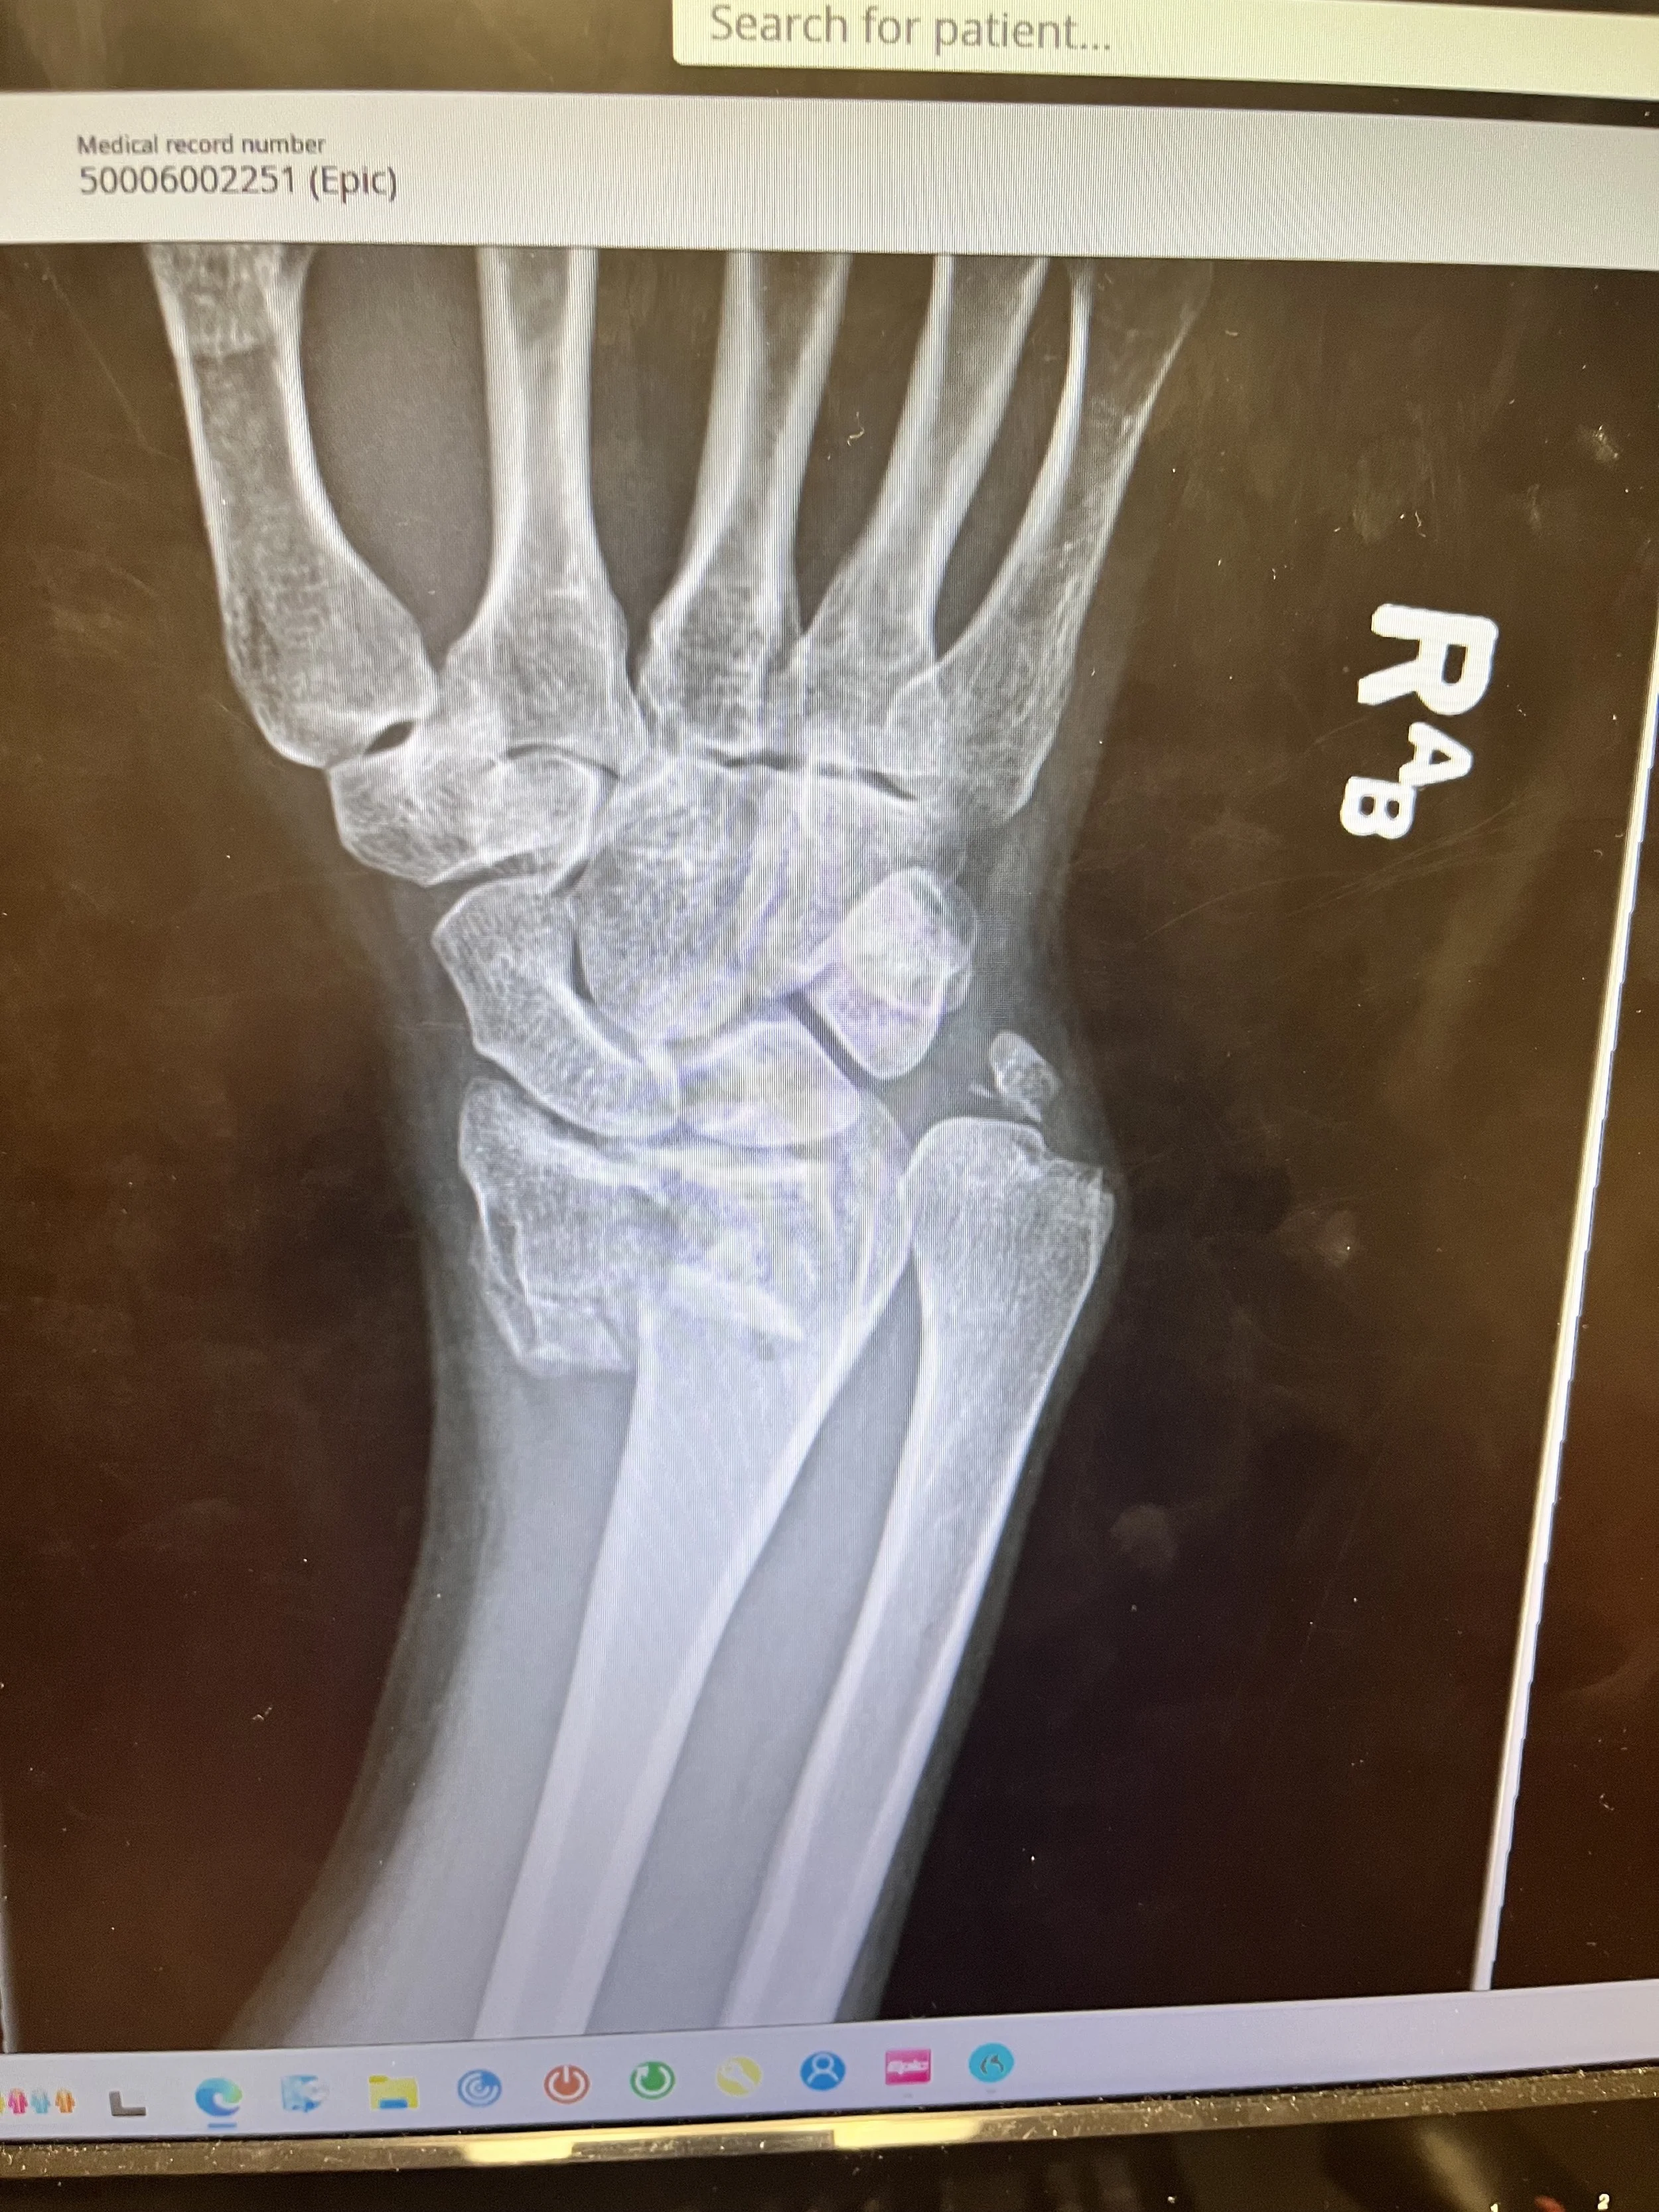

A Visual Glimpse into My Healing Journey

For those who are curious, I wanted to share a few photos from this chapter of my healing process — from the hospital to home, and the many small steps in between.

Some of the images include medical details like X-rays and surgical healing, which may be a bit sensitive for some. If you'd prefer to skip those, feel free to scroll past or stop here. Otherwise, I invite you to witness the journey with me — not just the clinical details, but what it’s been like to navigate all of this from my couch, my kitchen, and everything in between.

🦴 The Beginning of the Journey

This was my initial X-ray — showing a distal radius fracture with ulnar styloid involvement. The bones had shifted significantly out of place, making surgery necessary to realign and stabilize the wrist. I remember feeling shock, pain, and a deep knowing that this would be a long road — but also a sacred one.